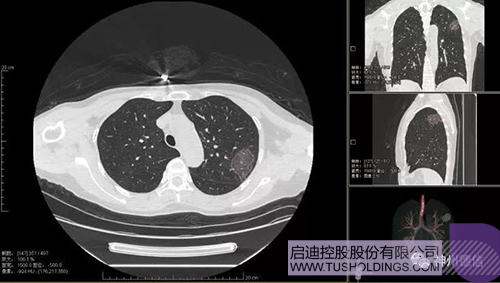

神州德信新冠肺炎检测及智能量化分析系统

九游电子娱乐_九游体育(中国)战略投资企业神州德信作为国内领先的肺部影像人工智能企业,针对新型冠状病毒肺炎开发了智能检测及量化分析系统,并在陕西、重庆等地定点医院投入使用。该系统在疑似病例大规模快速筛查及精准诊断方面发挥了重要作用,特别是其具有的肺炎患者临床影像跟踪量化随访功能,为快速有效阻断疫情扩散提供了有力武器。